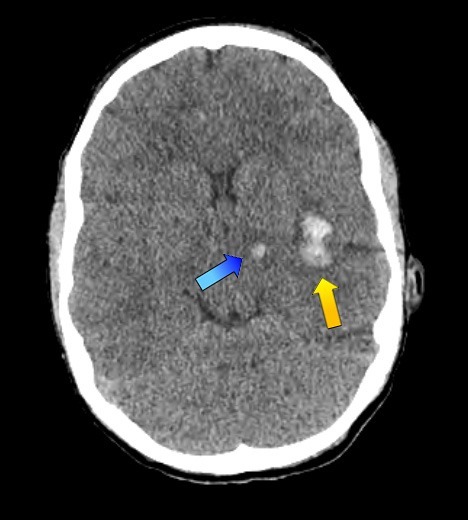

Have a look at the CT brain scan show in Figure 1. Notice the two haemorrhages, a small one in the dorsolateral thalamus (blue arrow) and a larger bleed in the region of the insula (yellow arrow). This is a standard radiological image. We’ve been using them for decades.